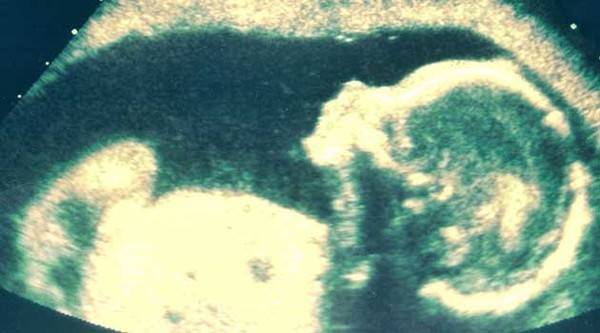

Во старицата од 82 години, која дошла во болница во Колумбија заради болки во стомакот,лекарите во абдоменот откриле скаменет фетус, односно литопедион.

Литопедион е редок медицински феномен кога фетусот не се развива во матката туку во стомакот.

Во овој случај фетусот се префирлил во делот на абдоменот каде не постои можност да се развие. Станал калцифициран фетус бидејќи телото на тој начин се борело против него – објаснил др. Камер Рамирез.